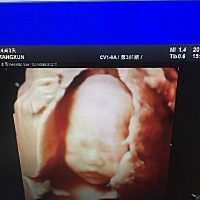

有谁能会看出是男宝女宝吗?